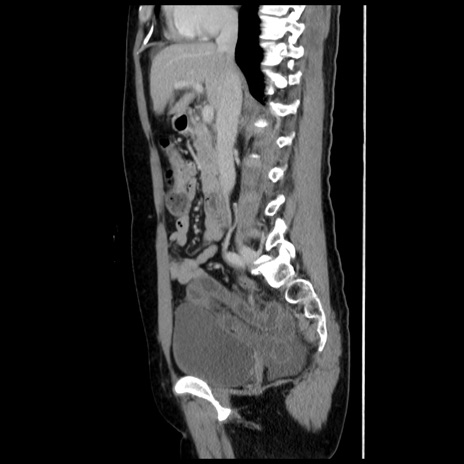

症例10(矢状断像)

【症例】 50歳代女性

【主訴】 腹痛

【現病歴】前日生レバーを食べた。今朝に排便あり。 昼前に突然発症の腹痛を生じ、当院救急外来を受診した。

【既往歴】 子宮筋腫にてで子宮全摘後

【身体所見】 意識清明、腹部:平坦、軟、下腹部やや左を中心に圧痛・反跳痛あり、筋性防御あり

【データ】WBC 7800、CRP 0.07